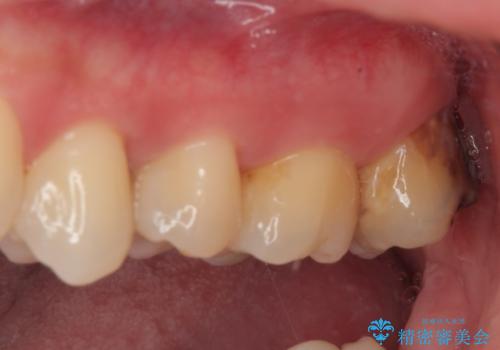

矯正治療により処置が可能な位置に歯が移動したため、オールセラミッククラウンにて補綴治療を行うこととしました。

歯列が移動したとはいえ、左右ともに後方傾斜しており、むし歯の除去、形成(形を整える)、型取りの全てが非常に困難な処置となりました。

セラミッククラウンの適合はレントゲン写真からも分かる通り、境界がぴったりと合った、高適合のものとなりました。